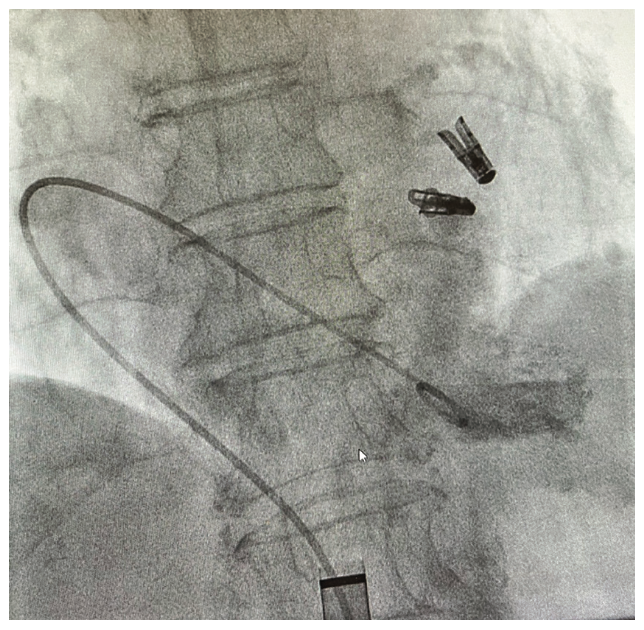

Rarely, implantation attempts are aborted due to patient anatomy, especially in those with significant scoliosis, creating an acute angle at the inferior vena cava-right atrial junction. Combined with a small cardiac size, the delivery system does not have the capability to safely prolapse into the RV, as compared to a conventional pacemaker lead (Figure 3, Video).